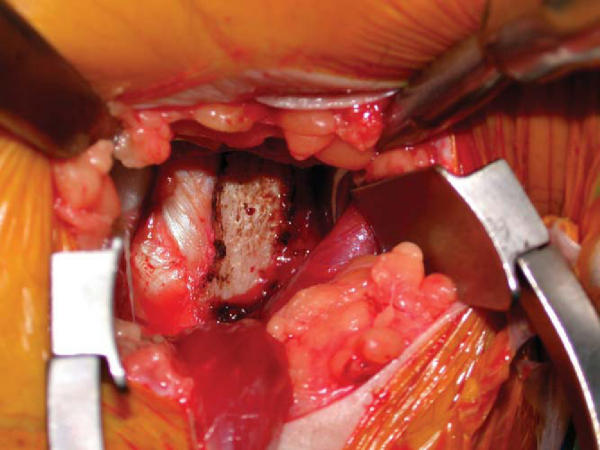

Blunt dissection with Mayo scissors and finger dissection sweep posterior to the pectoralis major tendon. The biceps tendon can be palpated in the intertubercular groove behind the pectoralis major tendon. A pointed curved Hohman retractor is placed on the lateral humeral cortex to retract the pectoralis tendon insertion superior and lateral. A blunt Chandler retractor is positioned on the medial cortex to retract the coracobrachialis and short head of the biceps. Vigorous medial retraction should be avoided to prevent injury to the musculocutaneous nerve. The long head of the biceps musculotendinous junction should be visualized. A right-angled clamp is then used to bluntly open the biceps sheath and deliver the tendon into the wound (

Fig. 27-4

).